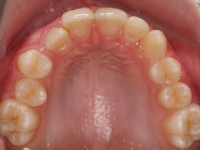

El paciente A.J. de 11 años, acude a nuestra consulta con apiñamiento maxilar importante. El canino lateral (12) está en mordida cruzada. Presenta una Clase II molar y canina, y la línea media está desviada. Se realizó un tratamiento con brackets autoligables metálicos de smartclip 022. La duración del tratamiento fue de 22 meses.

El paciente actualmente ha terminado el tratamiento con brackets y lleva una contención fija de 2-2 en maxilar y 3-3 en mandibular; para complementar también lleva una férula ESSIX durante la noche.